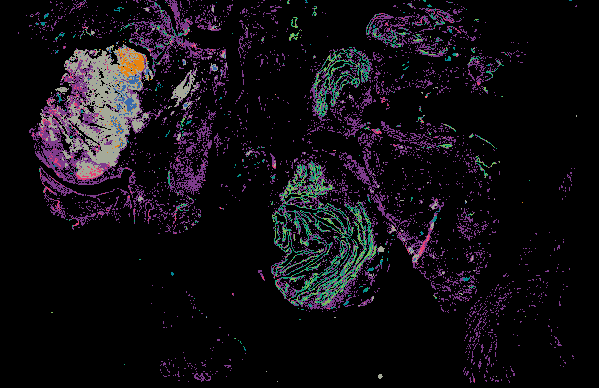

Serous Tubal Intraepithelial Carcinoma (STIC) with BRCA2 Mutation (LSP18251) from 'Multimodal Spatial Profiling Reveals Immune Suppression and Microenvironment Remodeling in Fallopian Tube Precursors to High-Grade Serous Ovarian Carcinoma'.